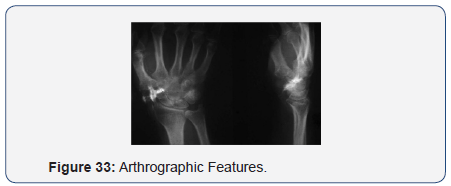

Arthrographic Features

- Distinct Joint Space - 25 wrists

- Comm. with midcarpal joint - 10 wrists

- Comm. with radiocarpal joint - 2 wrists

- Comm. with distal RU joint - 1 wrist

- Comm. with tendon sheaths - 4 wrists

- Contour-Irregular & small - 16 wrists

- Regular & larger - 9 wrists (Figures 33-36).